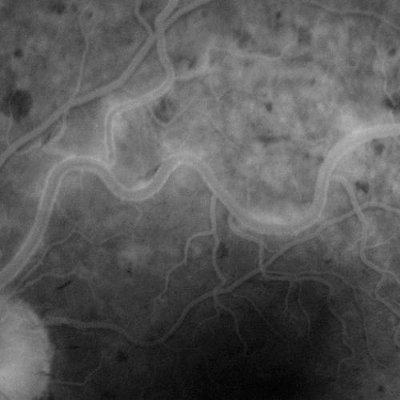

Colour photographs and green photographs are taken first of the retina usually of a 'straight ahead' view which will show the area of sharpest vision (macula). After that a butterfly needle or ventflon (plastic tube) is placed in an arm or hand vein and the dye is injected rapidly over 5 seconds. After around 14 seconds the dye starts to be seen circulating in the blood vessels of the retina and a rapid sequence of flash photos is taken for the first minute or so. After that photos may be taken of the peripheral parts of the retina usually four quadrants; and of the other eye. The last photographs are taken at 5 minutes from the initial dye injection.Shown below are two examples of flourescein angiograms. The first one shows a normal appearance. The dye passes through the blood vessels with no "blockages" and no leakage. The vessels look nice and sharp. Take a look at the second one and you will see the dye "leaking" out of the blood vessels, which look rather fuzzy. this angiogram comes from a patient who has active uveitis.

2. Angiogram showing active inflammation